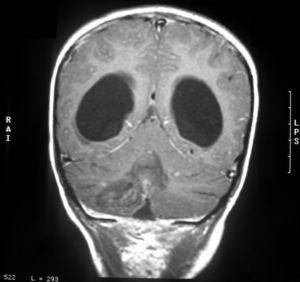

La tomografía computarizada (TC) cerebral con contraste mostraba una tumoración en el techo del cuarto ventrículo con calcificaciones, edema perilesional e hidrocefalia triventricular (fig. 1). Las resonancias magnéticas (RM) cerebral y de neuroeje con gadolinio confirma la presencia de la tumoración con una alta sospecha de ependimoma (fig. 2).

Figura 2.RM craneal coronal con gadolinio al diagnóstico. Tumoración de 3 cm de diámetro mayor, localizada en el cuarto ventrículo que desciende a través del agujero de Majendi, y que provoca una hidrocefalia obstructiva activa. Sospecha de ependimoma.